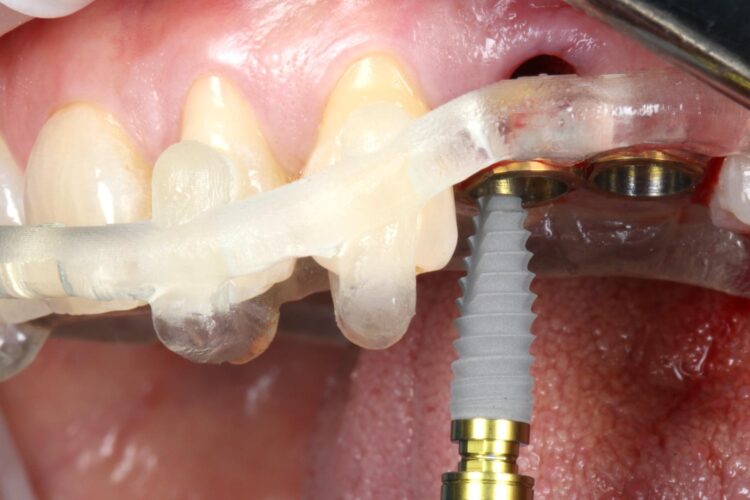

The surgical guide was then placed in the mouth and the manufacturer’s specific drilling sequence followed, increasing the osteotomy in size incrementally.

The CONELOG® Progressive implant 3.8mm is my go-to for premolar sites. The implant is versatile in its clinical application, suitable for use in healed ridges and fresh sockets, providing good stability for delayed and immediate implant placement protocols. It’s an all-in-one implant for me and I love using it.

Two 3.8mm diameter CONELOG® Progressive-Line implants were placed through the guide, following the plan precisely. The UL4 implant was longer (11mm) to ensure sufficient apical bone was engaged for primary stability, it was also positioned in the palatal root to ensure good engagement with the bone and better bone to implant contact. A sizable jump gap was noted between the implant and the buccal plate of around 5-6mm. From a biological perspective, the jump gap can be left because the ridge would heal to leave a sufficient buccal plate. However, the literature[iv] shows that grafting reduces the amount of bone resorption post implant placement, which was one of the reasons that augmentation was indicated in this case.